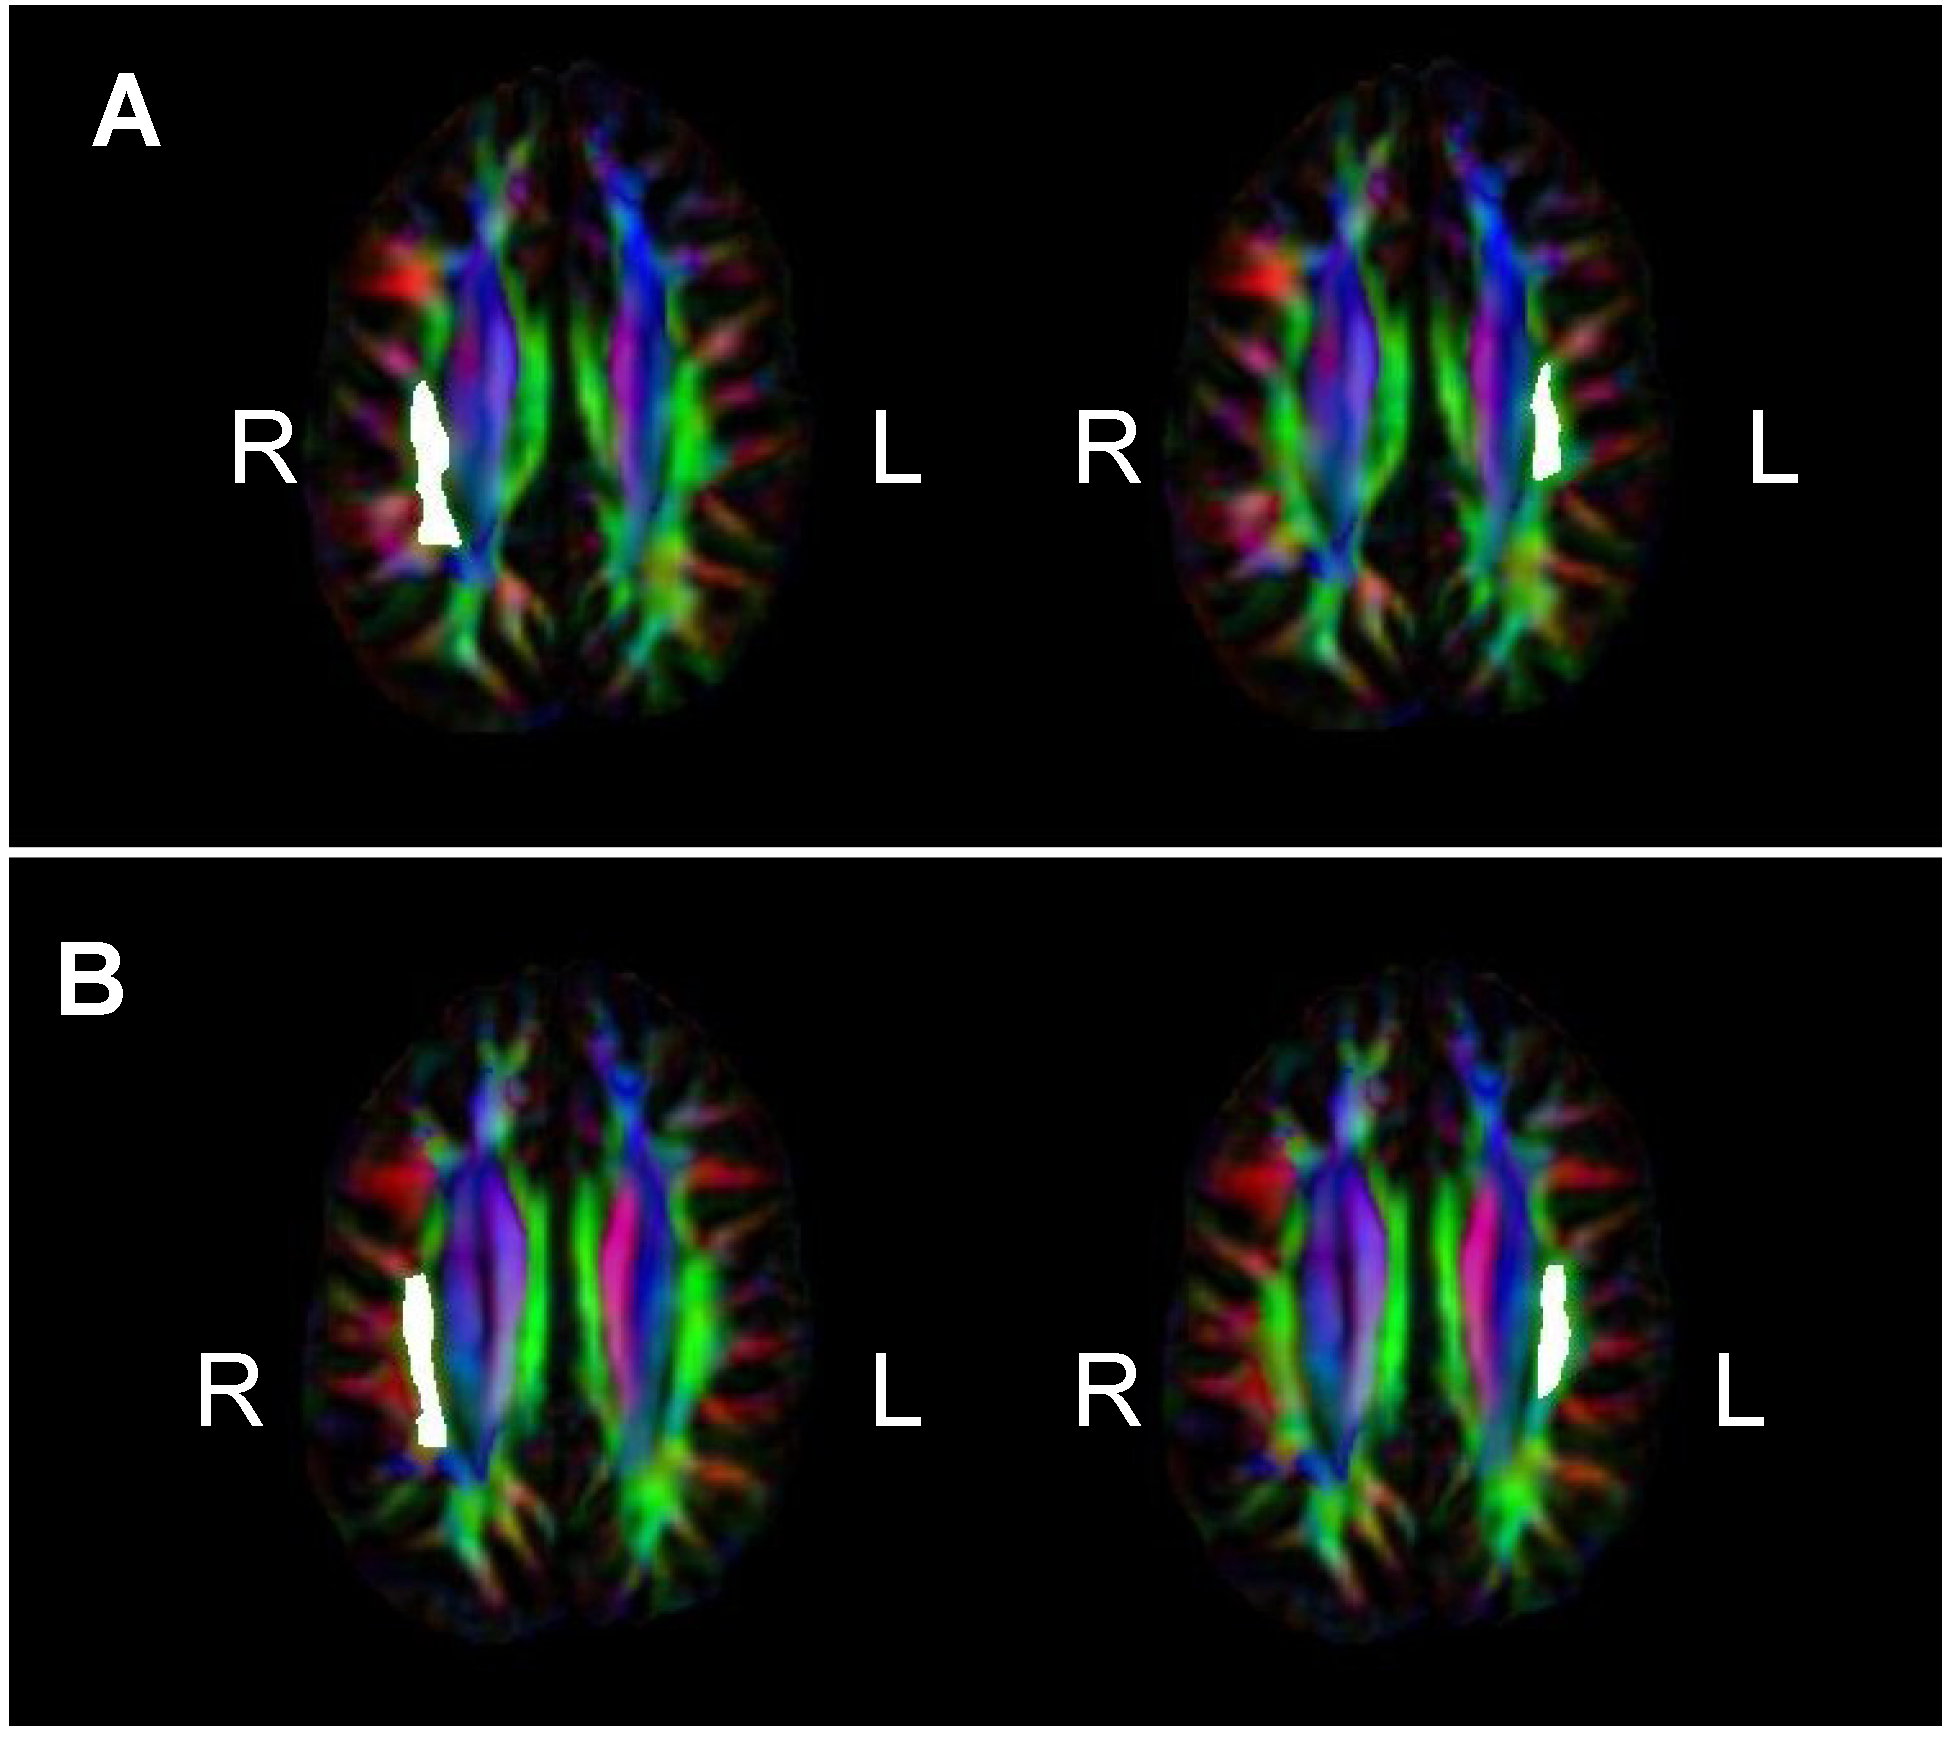

= Amusia. (A) DTT scores and white matter volume of right pars orbitalis (r = 0.507, p = 0.038); (B) DTT scores and gray matter volume of right pars orbitalis (r = 0.479, p = 0.052); (C) DTT scores and FA of right inferior SLF (r = 0.694, p = 0.002); (D) DTT scores and FA of right superior SLF (r = 0.506, p = 0.038).

= Amusia. (A) DTT scores and white matter volume of right pars orbitalis (r = 0.507, p = 0.038); (B) DTT scores and gray matter volume of right pars orbitalis (r = 0.479, p = 0.052); (C) DTT scores and FA of right inferior SLF (r = 0.694, p = 0.002); (D) DTT scores and FA of right superior SLF (r = 0.506, p = 0.038).

= Amusia. (A) DTT scores and white matter volume of right pars orbitalis (r = 0.507, p = 0.038); (B) DTT scores and gray matter volume of right pars orbitalis (r = 0.479, p = 0.052); (C) DTT scores and FA of right inferior SLF (r = 0.694, p = 0.002); (D) DTT scores and FA of right superior SLF (r = 0.506, p = 0.038).

= Amusia. (A) DTT scores and white matter volume of right pars orbitalis (r = 0.507, p = 0.038); (B) DTT scores and gray matter volume of right pars orbitalis (r = 0.479, p = 0.052); (C) DTT scores and FA of right inferior SLF (r = 0.694, p = 0.002); (D) DTT scores and FA of right superior SLF (r = 0.506, p = 0.038).